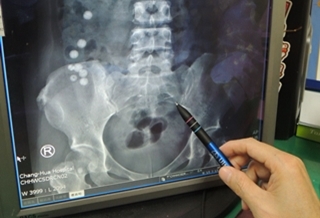

(優活健康網記者徐平/綜合報導)生鏽鐵釘穿腸卡肚2年竟沒事!一名疑有精神障礙的44歲婦女,日前因吞食小彈珠到院就診,神奇的是腹部除了有8顆彈珠外,竟然還有一根已斷成兩截的生鏽鐵釘卡在腹腔內,拒患者陳述該鐵釘在腹腔內2年都沒有排出,但卻沒引發腹膜炎等疾病,醫師利用腹腔鏡手術,取出小腸外、腹腔內的網膜處的2公分長的生鏽鐵釘。

彰化醫院肝膽腸胃科主任陳詩典表示,該名婦女吞了多顆彈珠,經照射X光發現,小腸處有8顆約1公分直徑的圓球物,而後病人又提及曾在2年前吞下鐵釘一直沒有排出,經仔細觀看X光,腹腔內確有兩段不明物體,經電腦斷層確認為外來物。

外科主任余明昌表示,一般而言,異物入肚最多的東西是大根的魚刺,外來異物刺穿小腸,會造成腹膜炎,若不馬上處理,還可能演變成敗血症,有生命危險,但該起個案,鐵釘刺穿小腸後,小腸卻自行癒合,沒引發後續的腹膜炎,而鐵釘就待在體內達2年,又不會疼痛,相當罕見。